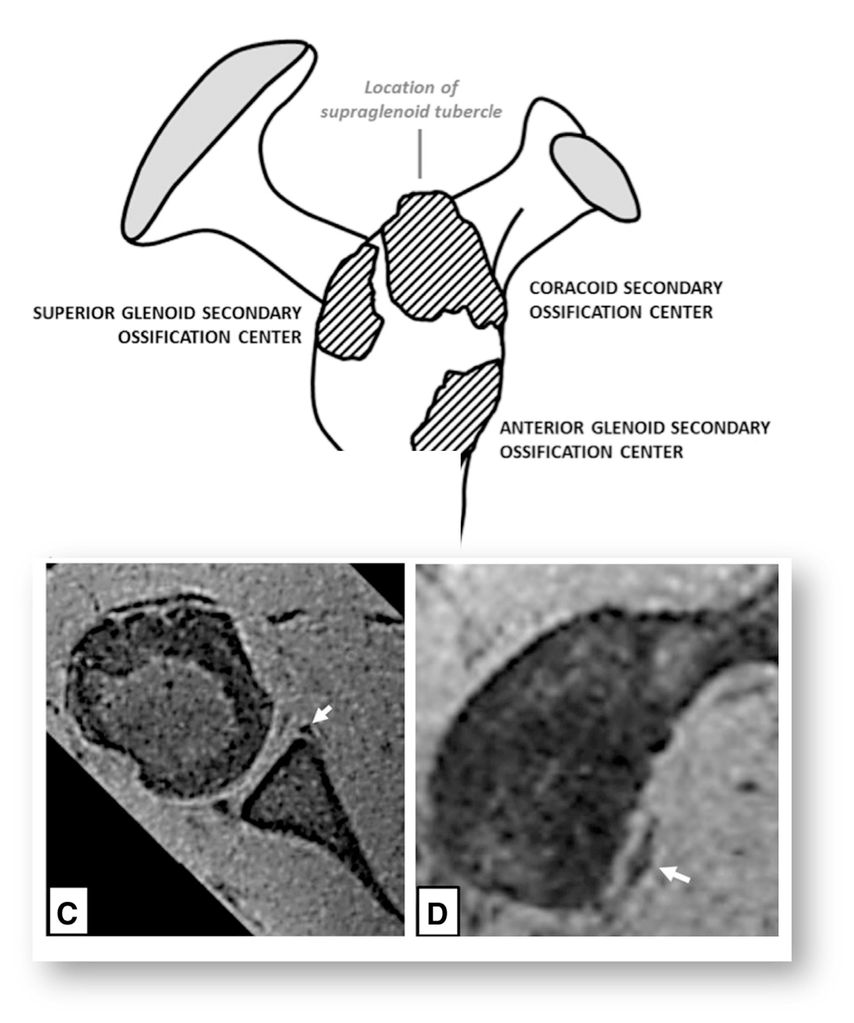

Das Hauptproblem ist die Tatsache, dass Instabilität eine funktionelle Problematik und nicht automatisch mit strukturellen Veränderungen assoziiert ist. Auf der anderen Seite können auch strukturelle Veränderungen auftreten, ohne dass eine Instabilität entsteht oder entstanden ist. So kann zum Beispiel die überweite Kapsel als kausale Pathologie für die multidirektionale Schulterinstabilität (MDI) am nativen MRI nicht beurteilt werden (Gefahr falsch negativ). Auf der anderen Seite können zum Beispiel die Wachstumskerne am anteroinferioren Glenoid, die regelmässig bis spät in die zweite Dekade nicht fusionieren, als ossäre Bankert-Läsion fehlgedeutet werden (Gefahr falsch positiv) (Abb. 1).

Abb. 1: Der anteroinferiore Knochenkern des Glenoids fusioniert erst in der 2. Dekade und kann mit einer Bankart-Läsion verwechselt werden. Nach Sidhartan et al., Arthroscopy 2020

Das Glenoid ossifiziert erst im Alter von 11–12 bzw. 11–17 Jahren (Mädchen/Jungen︎), es besteht daher die Gefahr eines falsch positiven MRI. Labrumläsionen sind trotzdem nicht ausgeschlossen, es zeigt sich im Kindesalter aber eine höhere Inzidenz von begleitenden Kapselverletzungen als bei Erwachsenen. Bei der Behandlung ist es dementsprechend wichtig, beide Probleme gleichermassen zu suchen, ein-/auszuschliessen und zu adressieren.